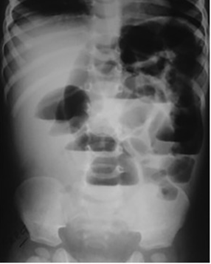

Note the presence of a gasless abdomen or paucity of gas (Figure 2), as well as excessive gas in either the small or large bowel. Additionally, observe the presence of gas in the rectum.

Figure 2 Anteroposterior supine abdominal radiograph in a 4-year-old child showing paucity of gas, few dilated small bowel loops with smooth walls (few valvulae conniventes can be seen), some gas visible in distal bowel loop suggestive of a proximal or high, partial small bowel obstruction.

The greater the number of dilated small bowel loops visible, the more distal the obstruction. Three or fewer dilated small bowel loops indicate a high or proximal obstruction (Figure 2& 7), while more than three dilated loops indicate a low or distal obstruction (Figure 6).3

High bowel obstruction is up to Jejunum whereas low obstruction is in ileum/ or colon. Both can be complete or partial. In complete obstruction (Figure 3), there is no gas distal to the site of obstruction whereas in partial obstruction, some gas is able to pass through the obstructed segment (Figure 2 & 7), resulting in the presence of gas distal to the obstruction.